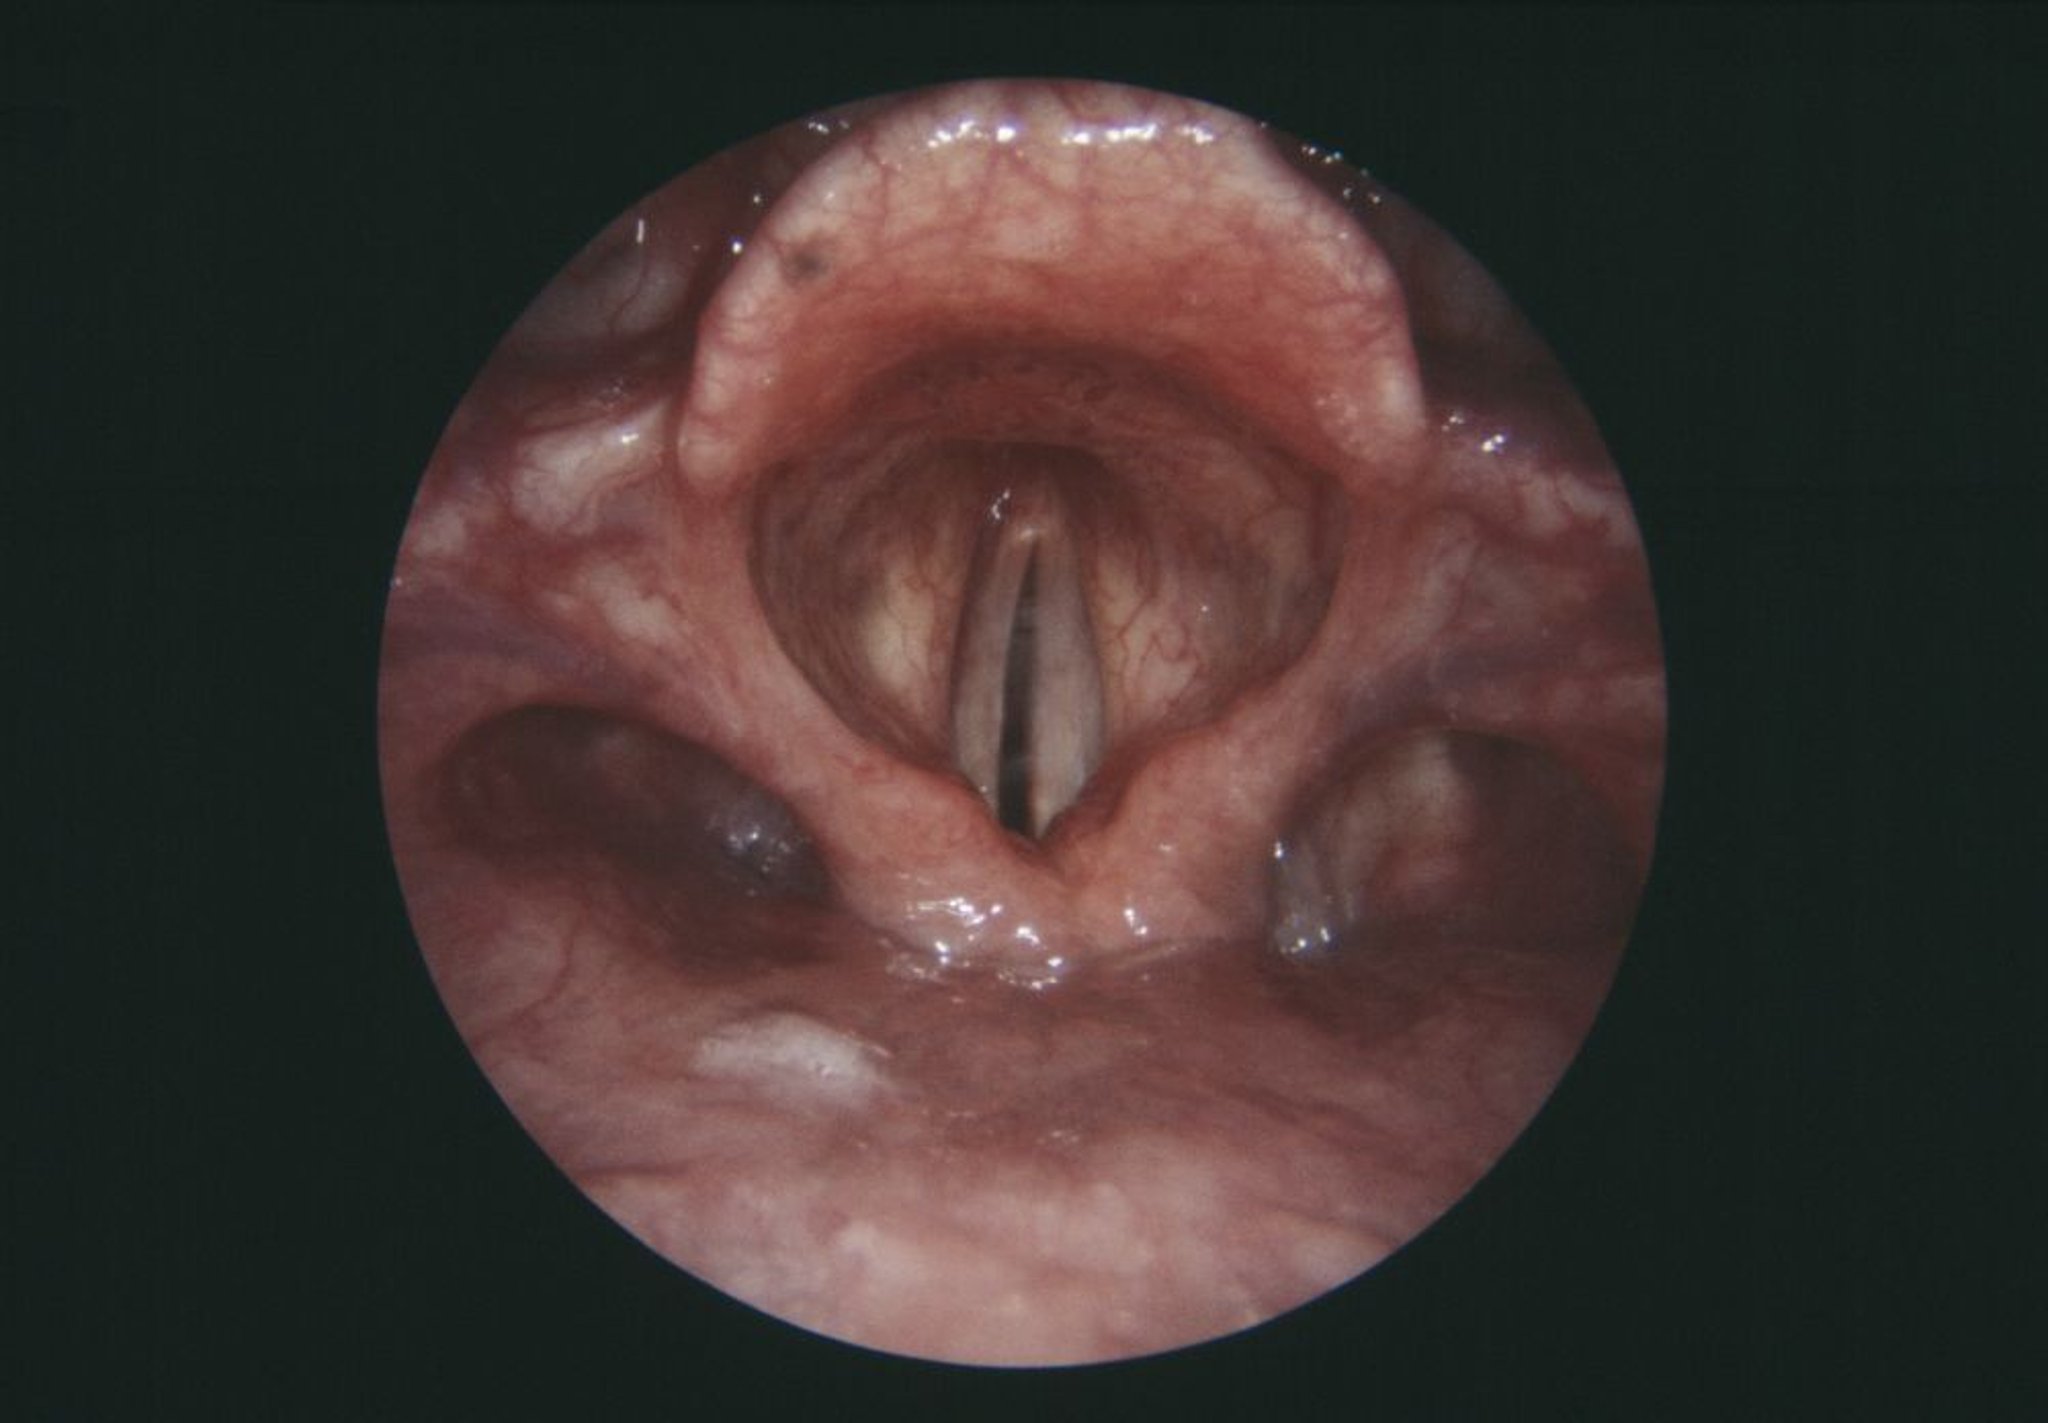

Essa visualização endoscópica da laringe (caixa de voz) mostra a prega vocal direita paralisada (cinza, centro esquerdo).